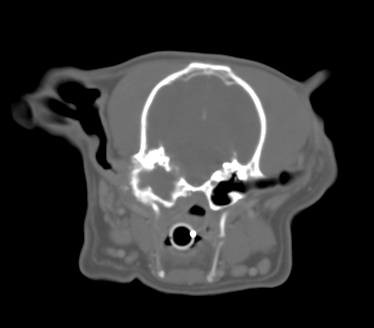

“Fencer” is a 9 year old Male (neutered) WHWT with a 12 month history of intermittent bilateral otitis externa. Fencer has had a left sided head tilt and also yelps with pain when yawning and refuses to eat his biscuits. Initial investigations are unrewarding with little response to NSAID therapy and topical ear medication based on culture/sensitivity. Fencer is anaesthetised and a CT examination performed (see below)

CT image

The left tympanic bulla is distorted and irregularly enlarged with areas of irregular bony proliferation and also osteolysis including erosion of the medial bulla wall towards the cranial vault. Some localised meningeal enhancement is visible suggestive of a meningitis. >>back to quiz

The most likely diagnosis is Cholesteatoma which is becoming increasingly frequently diagnosed. Other ddx would include a slowly growing primary middle ear neoplasm or otitis media (less likely).

Cholesteatoma is an epidermoid cyst that forms within the middle ear cavity. Contrary to what the name suggests, it is non-neoplastic and has nothing to do with cholesterol or fat. Rather, it is charaterised by a cornifying stratified squamous epithelium which produces keratin leading to a slowly expansile lesion within the tympanic bulla. The aetiology is incompletely understood but, although congenital forms are possible, they are most likely a result of chronic otitis externa in which keratinizing stratified epithelium has had the opportunity to seed and establish within the middle ear chamber.

Although in theory the cyst is benign, it can cause a range of signs relating to its position and size. Symptoms therefore include signs of otitis media – head tilt, nystagmus, circling etc but animals can also present as dogs who are reluctant to fully open their mouths and/or are reluctant to eat and this is due to encroachment of the cholesteatoma on the temperomandibular joint (TMJ). We have also seen some dogs which presented with dysphagia due to orpharyngeal compression from ventral outgrowth from the bulla. The lesions can also extend medially and erosion of the cranial vault can lead to otitis interna and even meningoencephalitis. >>back to quiz